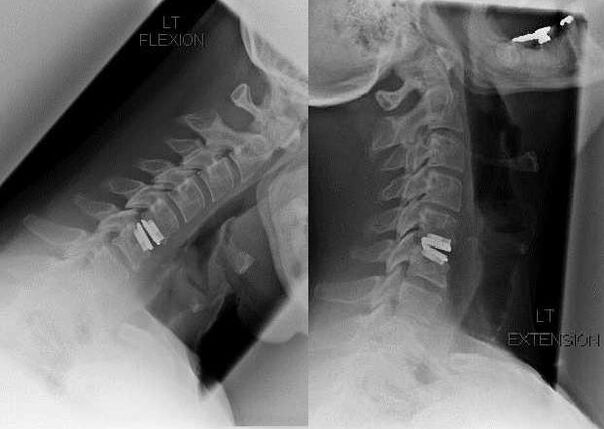

Surgical intervention

Indications for surgical intervention include ineffectiveness of conservative treatment, as well as complications of cervical osteochondrosis, for example, discogenic myelopathy, vertebral artery syndrome and radicular syndrome.To decompress the spinal cord, blood vessels and spinal roots, the following operations are performed:

During surgery, bone fragments and ligaments can be removed and the intervertebral discs can be removed completely or partially.For small herniated protrusions, laser vaporization of the disc core is often performed.

After removal of the vertebral structures, stabilization of the motion segments of the spine is often required by spinal fusion or installation of bone and dermal autografts.